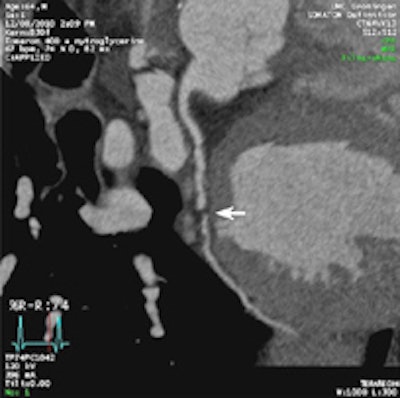

A 64-year-old patient with carotid stenosis. Top left: Coronary CT angiography image. White arrow points to a soft plaque in the midcircumflex artery, with stenosis of the lumen. Calcium score was 64. Top right: Short-axis image of the adenosine perfusion MRI examination. White arrow points to a perfusion defect in the posterolateral wall, during stress. The perfusion defect was not present in the rest series, thus indicating inducible ischemia. Bottom left: Invasive coronary angiography image of the left coronary arteries. Black arrow points to a significant stenosis, corresponding with the location seen on CT. Bottom right: Invasive coronary angiography image after intervention. Good results were achieved after percutaneous coronary intervention with stent placement. All images courtesy of Drs. Rozemarijn Vliegenthart and Martijn den Dekker.Two centers in the Netherlands scanned 115 cardiac-asymptomatic patients age 50 years and older (mean age 65 years; 76% men) with proven aneurismal or stenotic arterial disease with CT, MRI, and sometimes echocardiography as well.